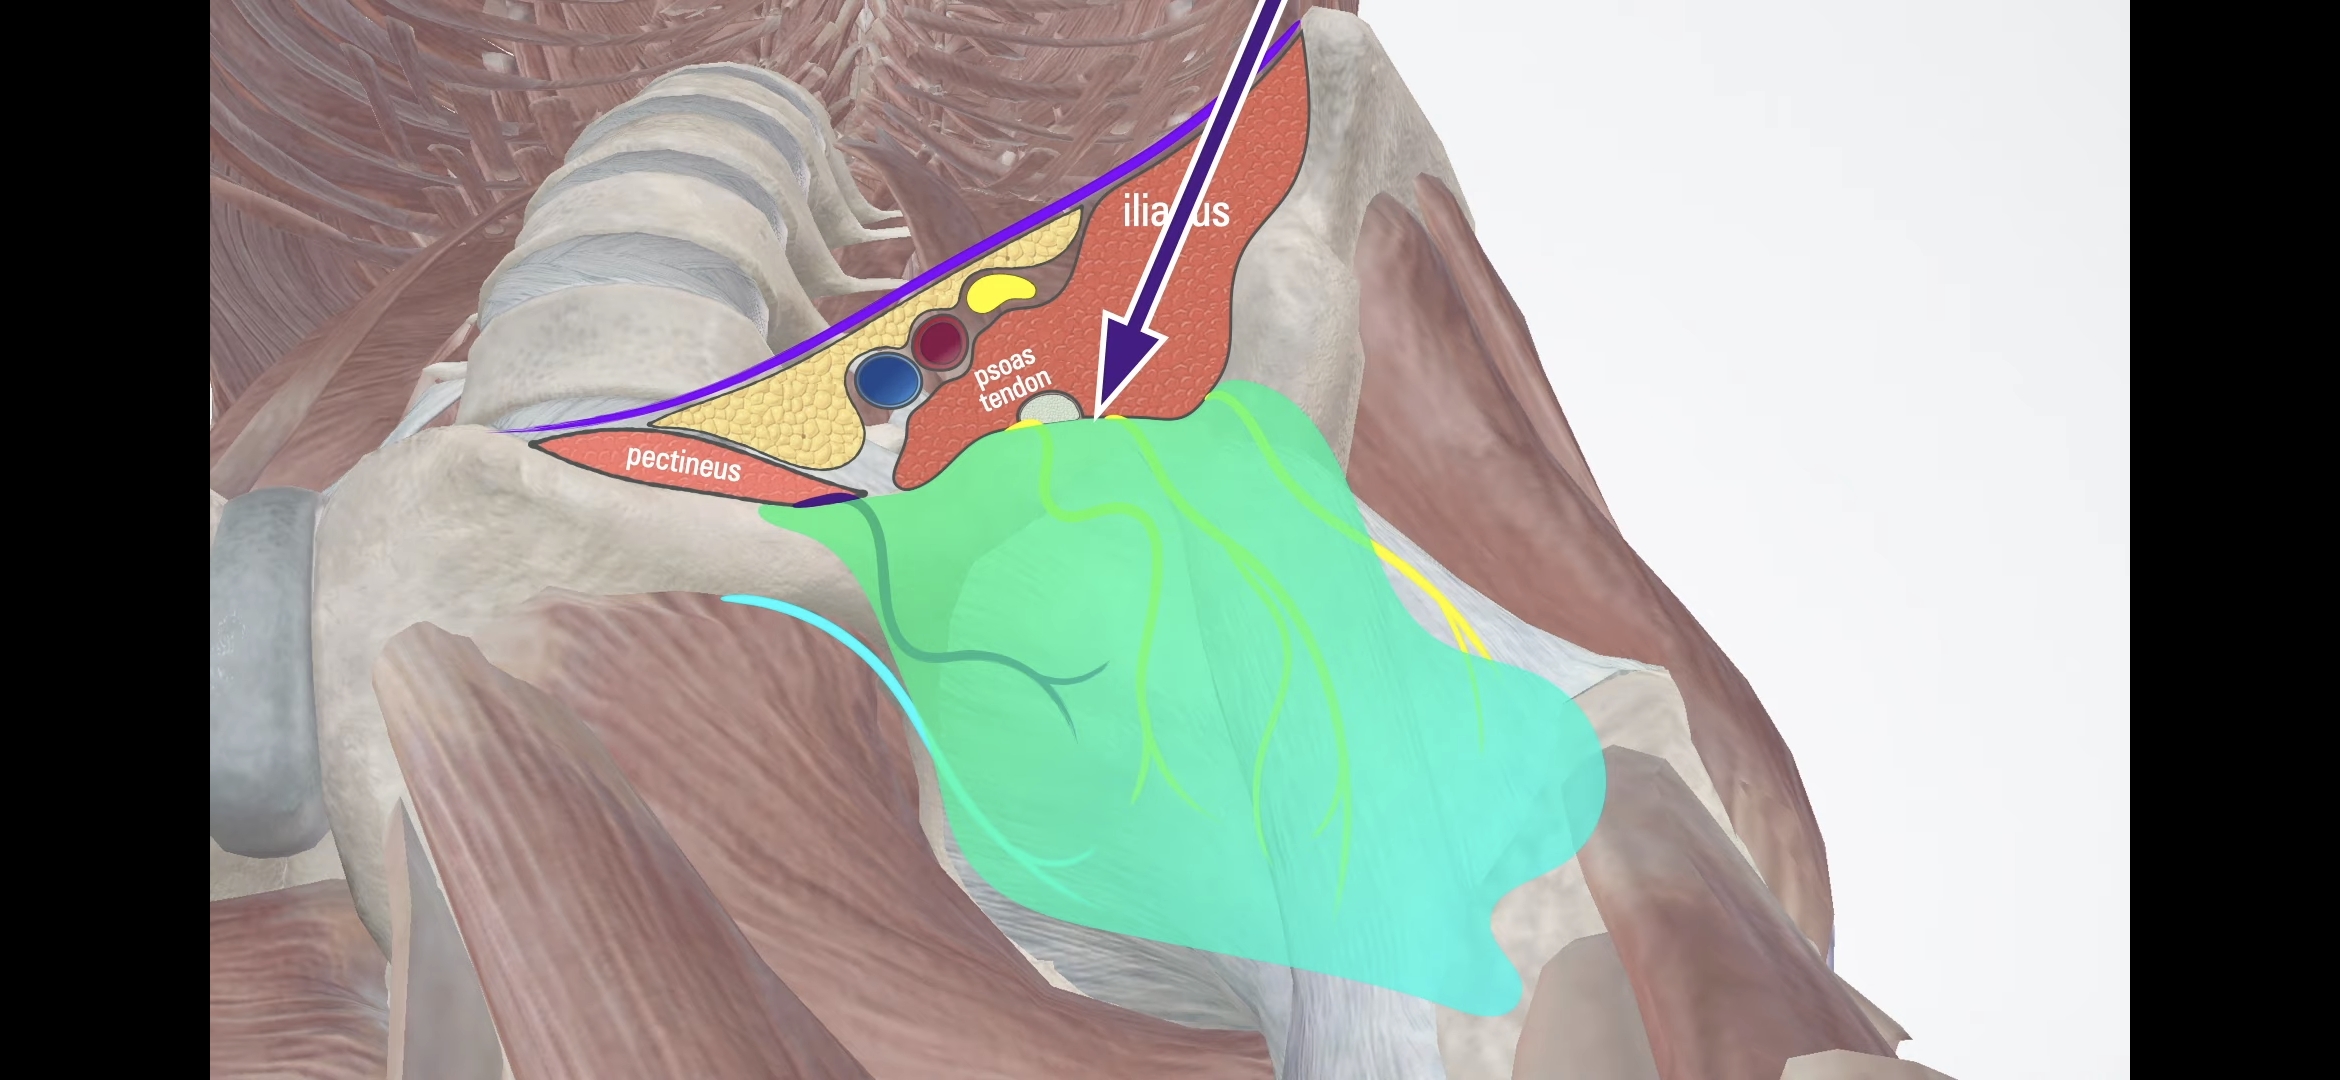

1. Pericapsular Nerve Group(PeNG) block

읽어 보니 사용한 방법은 두가지 신경 차단술이었다.

하나는 몇년 전부터 고관절 통증 관리, 특히 고관절 수술 후 통증 관리에 사용한 방법이고, 다른 하나는 내가 아는 신경 차단술이었다.

I. PeNG block

PeNG block + LFCN block